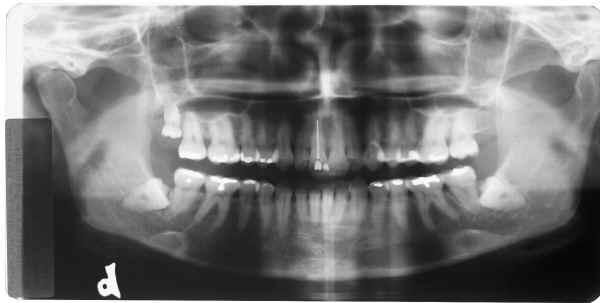

RX superior esquerdo

início

Rx superior direito

Rx inferior esquerdo

Rx inferior direito

Qual destes lados não foi editado?

Responda, justificando, e receba a resposta com as fotos originais!

Matematicamente a probabilidade de erro na 1ª resposta é igual a 75% = 3/4 x 100

Matematicamente a probabilidade de erro na 2ª resposta é igual a 50% = 1/2 x 100

Não aposte sua prova jurídica nisto, responda e verás!

Resposta da Primeira Questão

Radiografia 1

Radiografia 2

Radiografia 3

Radiografia 4